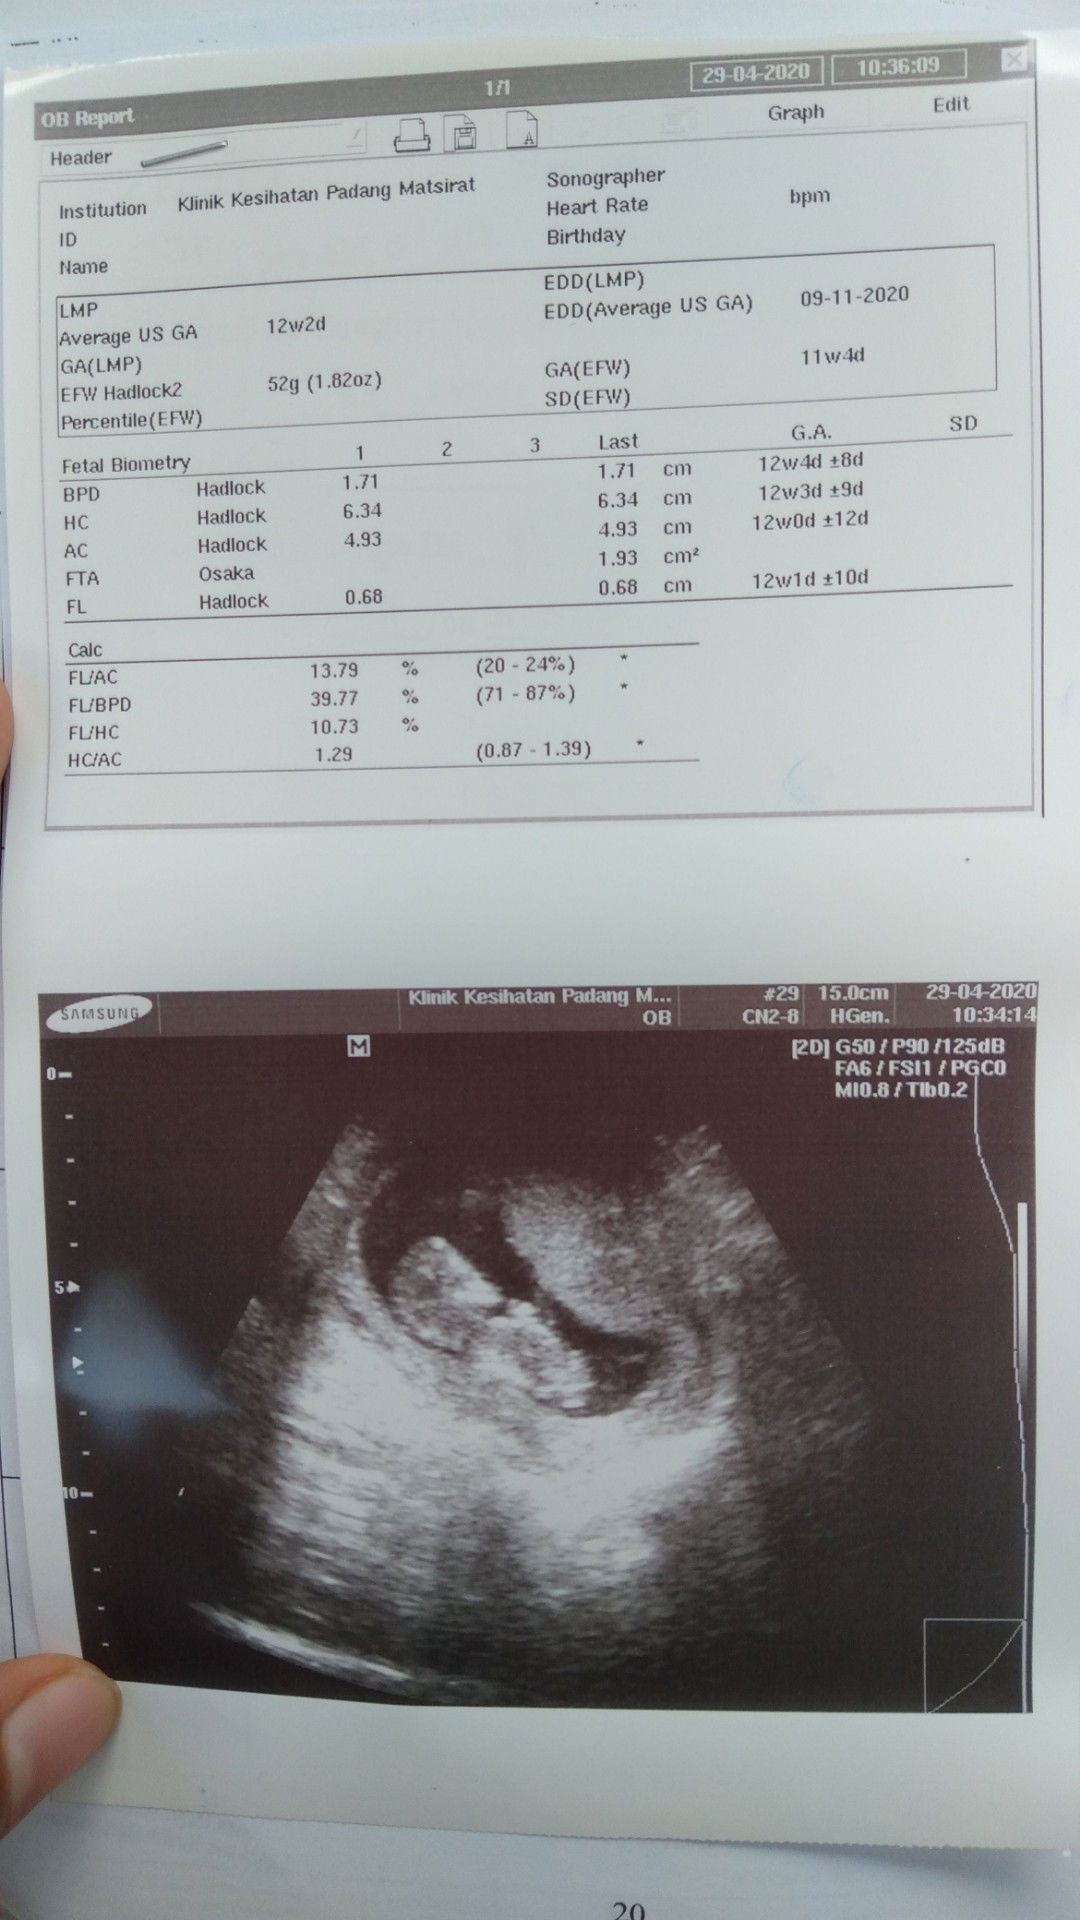

Masa first scan dapat due 23.11.2020 (scan klinik swasta) masa buat buku pink dekat klinik desa dapat due 19.11.2020. dan harini kena p scan dekat klinik kesihatan jumpa doktor. Dan dapat due 9.11.2020. lepastu doktor cakap due dengan klinik desa jauh beza. Lagi dua minggu kena p scan pulak. Pernah ada pengalaman macam ni tak? Tu gambar yang baru scan harini